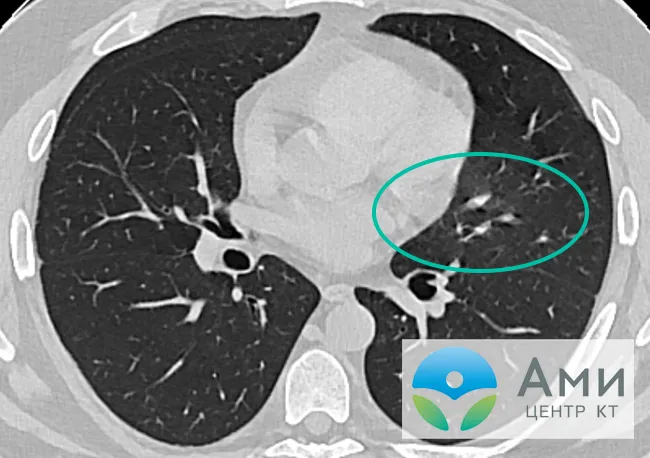

Компьютерная томография (КТ) – это мощный инструмент визуализации, который позволяет получить детальные изображения внутренних органов․ В случае фиброза легких, КТ может выявить характерные изменения в структуре ткани, такие как сотовое легкое, тракционные бронхоэктазы и ретикулярные изменения․ Однако, эти изменения могут быть очень тонкими и трудно различимыми на ранних стадиях заболевания․

Именно здесь на помощь приходит ИИ․ ИИ-системы, обученные на огромном количестве КТ-снимков с подтвержденным диагнозом фиброза, способны распознавать даже самые незначительные изменения в структуре легких․ Они анализируют каждый пиксель изображения, выявляя паттерны, которые могут указывать на наличие фиброза․ Затем, система предоставляет врачу отчет с указанием наиболее подозрительных участков и оценкой вероятности наличия заболевания․

На ранних стадиях фиброза изменения в легких могут быть минимальными и легко пропущенными․ Однако, ИИ, благодаря своей высокой чувствительности и способности к анализу сложных паттернов, может выявить даже самые незначительные отклонения от нормы․ Это позволяет нам начать лечение на ранней стадии, когда оно наиболее эффективно․